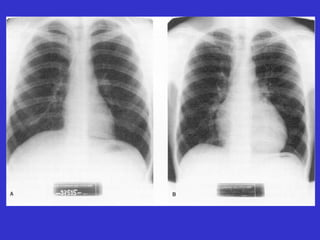

• #156 Figura 11.9 (Nuestro) Dos radiografías de torax, en las que se aprecia la diferencia de tamaño entre las siluetas cardiacas de un sujeto sedentario (A) y un ciclista (B)